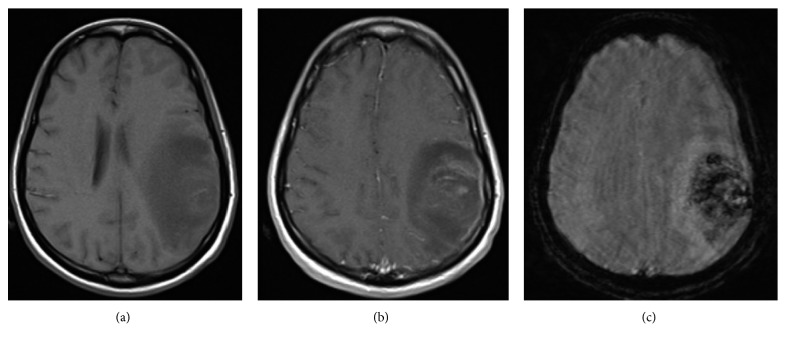

Figure 4.

On day 16, corresponding axial T1 precontrast (a) and postcontrast image (b) does not demonstrate rim enhancement or a fluid cavity to suggest an abscess. Additionally, except for some thin patchy postcontrast enhancement in the region of the vasogenic edema (which could represent some venous engorgement secondary to mass effect), no mass-like postcontrast enhancement is noted to suggest an enhancing tumor. (c) Corresponding susceptibility-weighted image demonstrates ill-defined areas of hemosiderin deposition in the left frontoparietal region representing areas of hemorrhage.